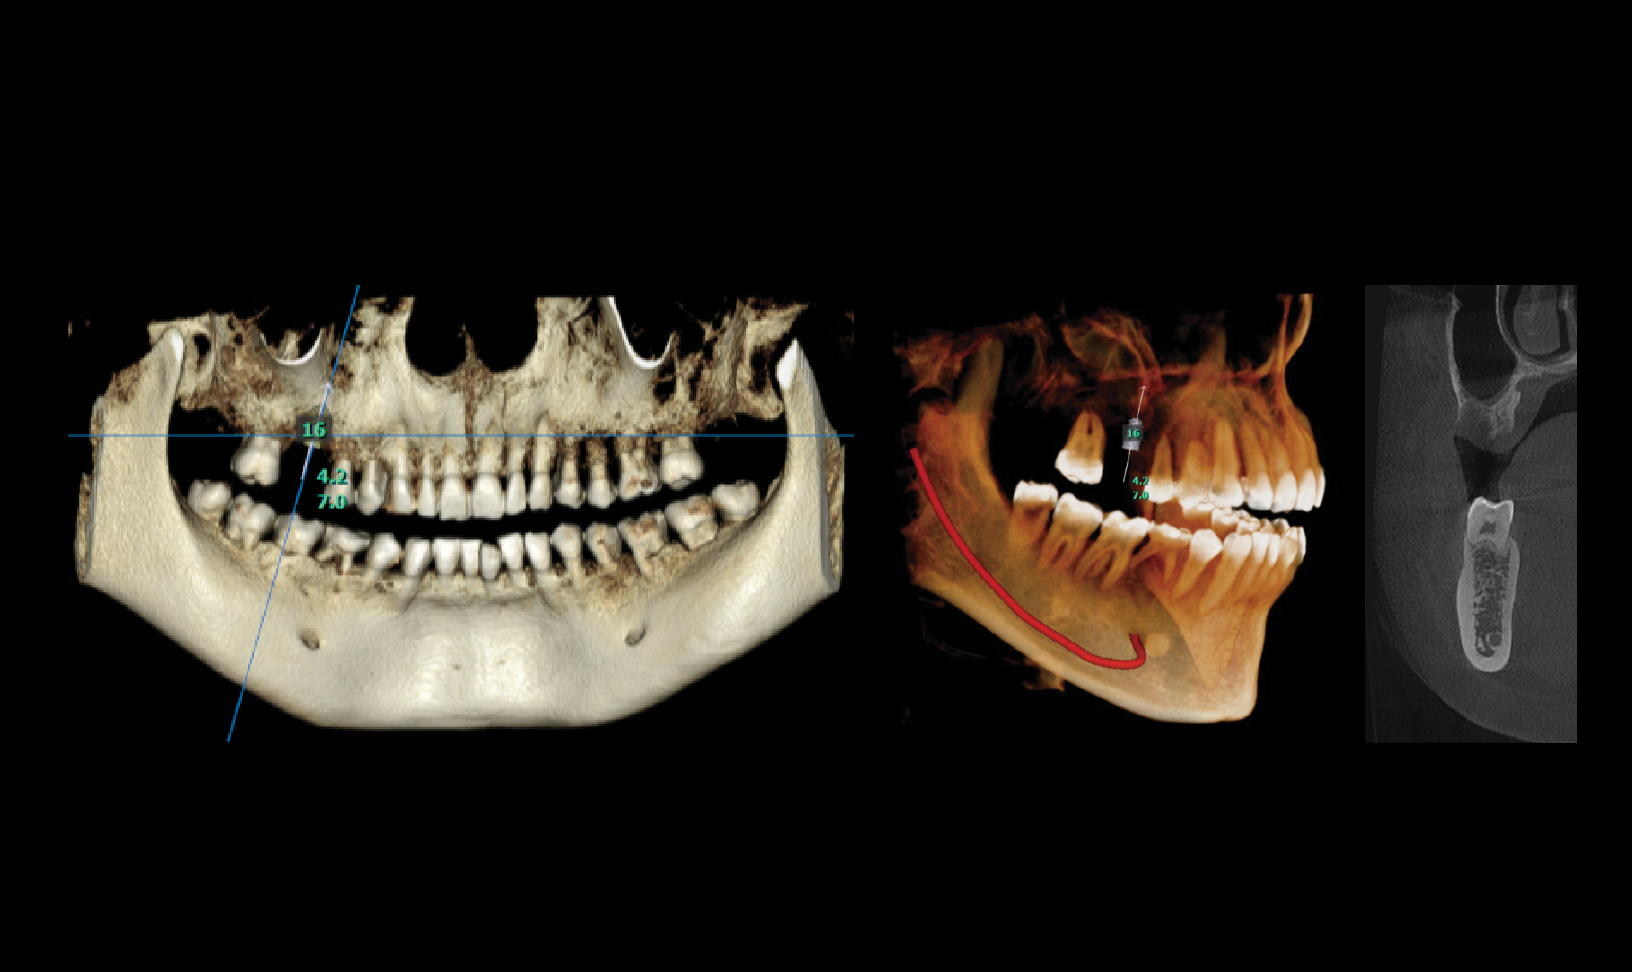

High Definition Imaging For Implants and Orthodontics

The RAYQuantum provides high-resolution 150-micron imaging for precise diagnostics and detailed assessments, making it ideal for implant procedures and optimal treatment planning.

High Definition Imaging For Implants and Orthodontics

The RAYQuantum provides high-resolution 150-micron imaging for precise diagnostics and detailed assessments, making it ideal for implant procedures and optimal treatment planning.